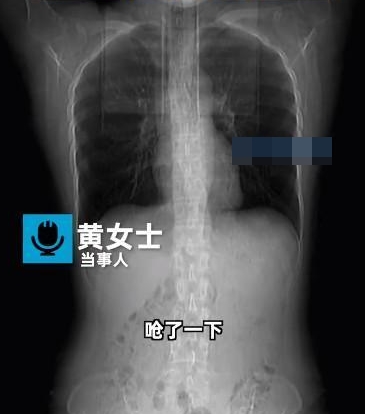

ภายหลังจากแพทย์ทำการเอกซเรย์ให้คนไข้หญิง พบว่า กระดูกซี่โครงซี่ที่ 5, 6 และ 7 ทางด้านขวา และซี่โครงซี่ที่ 6 ทางด้านซ้าย มีอาการแตกร้าวทั้งหมด แต่การตรวจเพิ่มเติมอื่น ๆ อาทิ ความหนาแน่นของกระดูก ไม่พบความผิดปกติ ศัลยแพทย์ทรวงอกจึงวินิจฉัยว่า เหตุเพราะคนไข้ผอมจนเห็นซี่โครงชัดเจน ไม่มีกล้ามเนื้อพยุง ทำให้ไอและกระดูกหักได้ง่าย